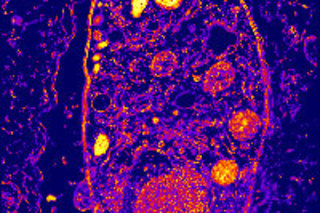

Stranger still, parasitologist Jaroslav Flegr of Charles University in Prague thinks T. gondii could also be skewing our sex ratios. When he looked at the clinical records of more than 1,800 babies born from 1996 to 2004, he noted a distinct trend: The normal sex ratio is 104 boys born for every 100 girls, but in women with high levels of antibodies against the parasite, the ratio was 260 boys for every 100 girls. Exactly how the parasite might be tipping the odds in favor of males isn't understood, but Flegr points out that it is known to suppress the immune system of its hosts, and because the maternal immune system sometimes attacks male fetuses in very early pregnancy, the parasite's ability to inhibit the immune response might protect future boys as well as itself.